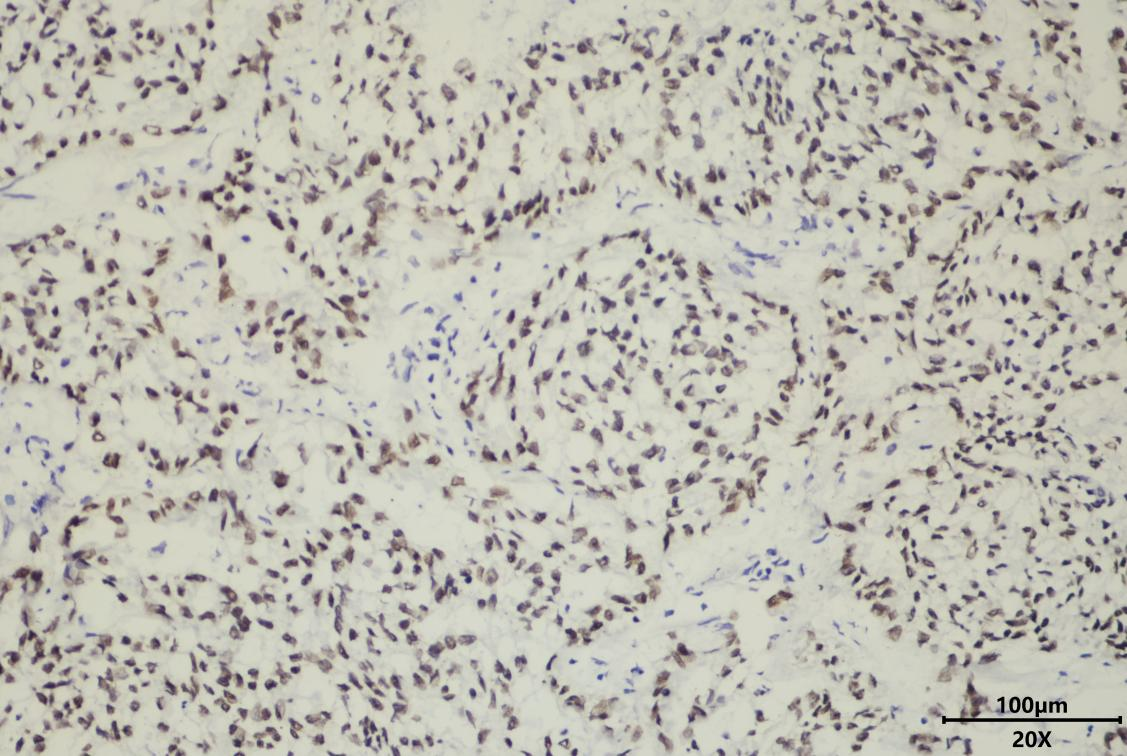

肺神经内分泌瘤术中冰冻TTF1免疫组化染色